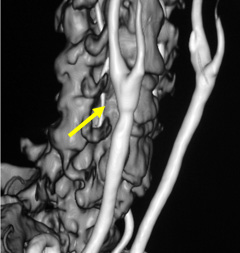

写真左:頚動脈狭窄所見

写真右:ステントを用いて狭窄部を拡張し治療